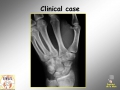

Scaphoid fracture